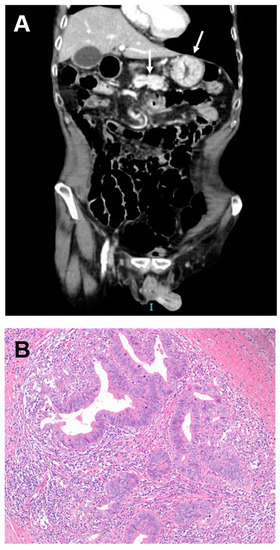

| Svrcek M et al., 2014 [8] | 41 | 47 | NA | 13.5 | 19/41 (46) | NA | 40/41 CrD-SBC were observed in inflamed mucosal areas. Flat or raised dysplasia was found in 20/41 patients with CrD-SBC |

| Grolleau C et al., 2017 [10] | 9 | 46, 37–67 | 36, 10–67 | 15, 0–32 | 5/9 (56) | 56 at 2 yrs | Adjacent dysplasia was present in 9/9 CrD-SBC |

| Bojesen RD et al., 2017 [12] | 23 | 53, 37–85 | NA | NA | NA | 26 at 5 yrs | 79% of CrD-SBC showed inflammation-dysplasia-carcinoma sequence |

| Vanoli A et al., 2017 [2,7] | 25 | 59, 33–84 | 50, 22–84 | 13, 0–41 | 13/25 (52) | 38 at 5 yrs | CrD-SBC exhibit a low rate of MSI and TILs CrD-SBC are associated with dysplasia and metaplasia, both showing gastropancreatobiliary phenotype |